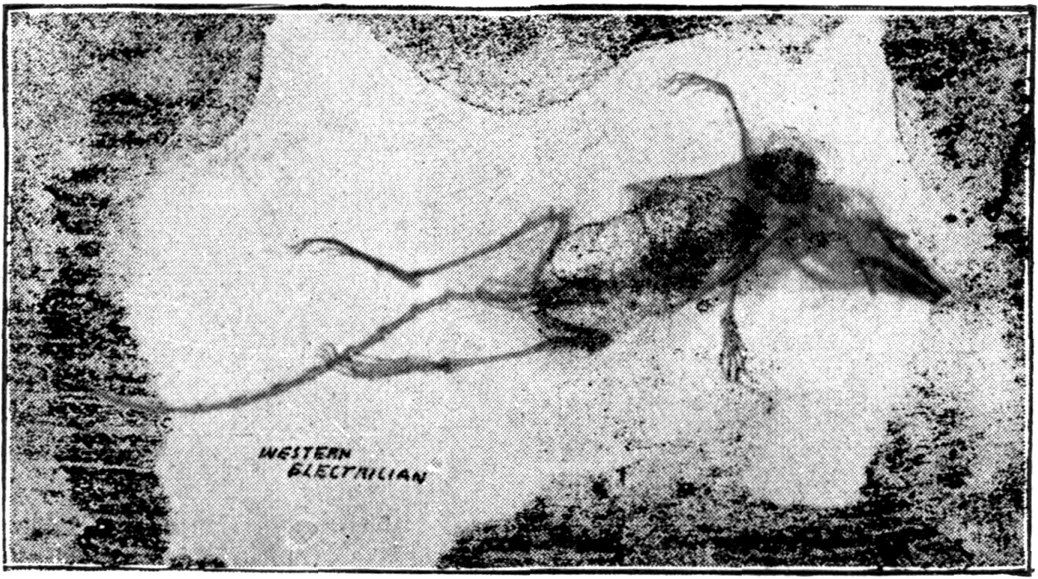

Fig. 1.—Head.

Fig. 2.—Broken Arm, Overlapping.

(Due to defective setting.)

Fig. 3.—Ribs.

Fig. 4.—Knee, Knickerbocker Buttons, Bullet in Femur.